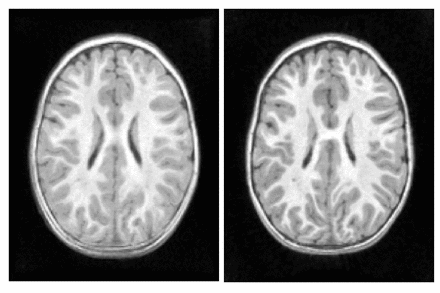

We explore the impact of joint image and shape regression in modeling pediatric brain development. The data consists of T1W images of the same healthy child observed at 6, 12, and 25 months of age. Regression on images alone is difficult in this case due to the very low contrast in the 6 month old image. Despite the low contrast, tissue segmentations can still be reliably and consistently estimated [10]. We estimate a geodesic model using only T1W images and a model jointly on images and white matter surfaces to emphasize the development of the tissue interface.

The results of geodesic regression are shown for several snapshots in time in Fig. 3. The model estimated using only images mostly captures the scale change, but does not capture much deformation in the interior of the brain. The model estimated jointly on image and shape captures more detailed development as white matter stretches and expands.

Fig. 3. Images and deformations estimated by geodesic regression using images alone (top) and jointly on images and white matter surfaces (bottom). Regression jointly on image and shape results in a more realistic evolution which captures detailed changes in brain tissue in addition to the increase in brain size. In both cases, geodesic regression was estimated backwards in time.